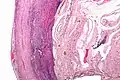

Pathology diagnosis of appendicitis can be made by detecting a neutrophilic infiltrate of the muscularis propria.

Micrograph of appendicitis and periappendicitis. H&E stain

Micrograph of appendicitis showing neutrophils in the muscularis propria. H&E stain

Acute suppurative appendicitis with perforation (at right). H&E stain